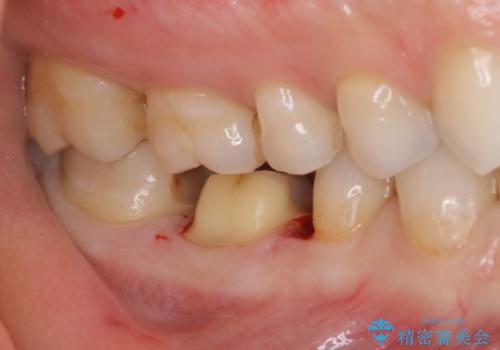

- 歯と歯の間によくものが詰まるということで来院された患者様です。

銀歯のある部分によくものが詰まるようで、診断の結果セラミックにて治療を行う計画を立てて

銀歯を外し他の歯も虫歯があったためそちらも一緒に治療を行いました。